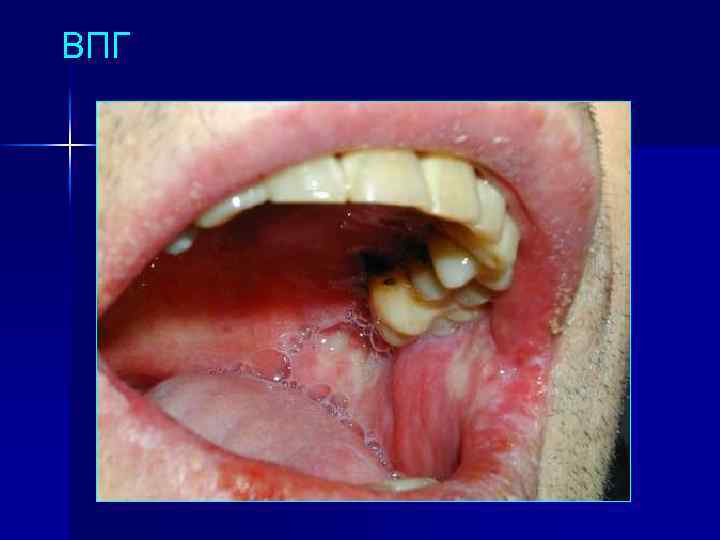

ВПГ

Оппортунистические поражения ЖКТ у ВИЧ-инфицированных n Поражение ротовой полости: – – n n Candida albicans – кандидоз Herpes simplex virus – афтозно-язвенный гингивостоматит Cytomegalovirus – афтозно-язвенный стоматит ВЭБ, ВПЧ – «волосатая» лейкоплакия Поражение пищевода: эзофагит, вызванный Candida spp. , Cytomegalovirus, HSV Поражение кишечника: цитомегаловирусный энтероколит, вызванный ВПГ, сальмонеллез (часто Salmonella typhimurium), криптоспоридиоз, микроспоридиоз и др.